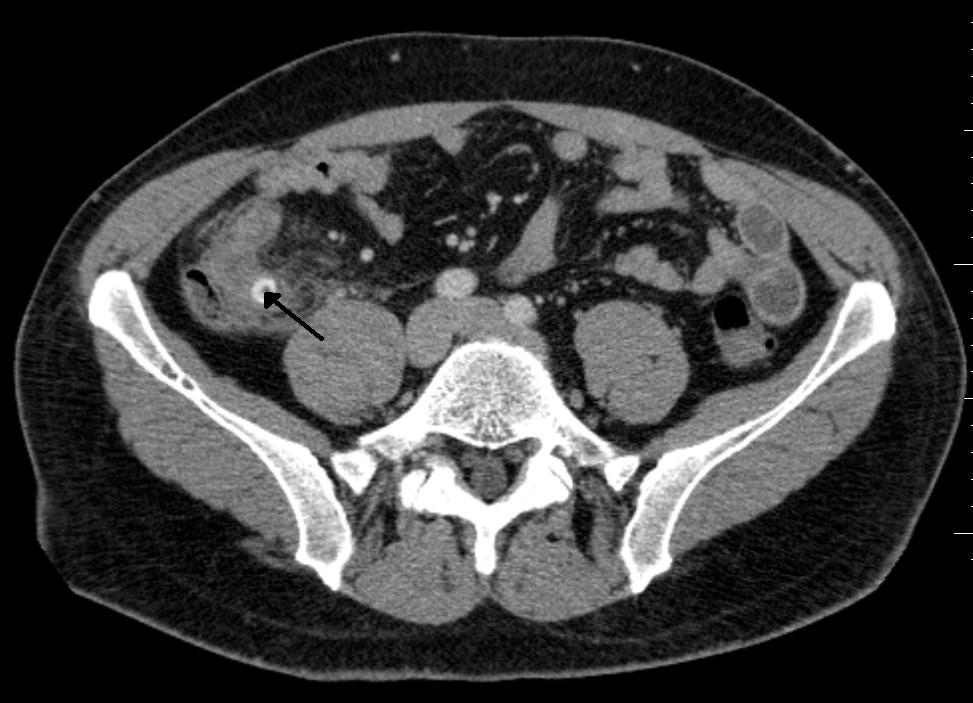

CT 스캔은 급성 충수염을 진단하는데 사용된다.[36] 의사는 환자의 병력과 증상을 평가하고, 신체 검사를 시행하며, 검사실 및 영상 검사를 모두 주문한다. 비전형적인 증상을 보이는 경우에는 초음파나 CT 스캔과 같은 영상 검사가 필요하다.[12] 소아는 방사선 노출 위험 때문에 초음파 검사를 우선적으로 시행하며, 결과가 불확실한 경우에만 CT 스캔을 추가로 시행한다.[54][55][56] 성인 및 청소년의 경우 CT 스캔이 초음파 검사보다 더 정확하며, 민감도 94%, 특이도 95%를 보인다. 반면 초음파 검사는 민감도 86%, 특이도 81%이다.[57]복부 초음파 검사, 특히 도플러 초음파는 특히 소아에게서 충수염 진단에 유용하다. 초음파 검사에서는 오른쪽 장골와에서 액체 저류, 컬러 도플러 사용 시 혈류 증가, 충수의 비압착성 등이 관찰된다. 급성 충수염의 다른 징후로는 충수 주변의 에코성 장간막 지방, 충수 결석의 음향 그림자 등이 있다.[58] 약 5%의 경우, 장골와 초음파 검사에서 이상이 발견되지 않지만, 이는 초기 충수염이거나 지방과 장내 가스로 인해 충수 확인이 어려운 성인에게서 흔하게 나타난다. 숙련된 검사자는 초음파 영상을 통해 충수염과 유사한 증상을 보이는 림프절 염증, 난소 또는 나팔관 문제 등을 구별할 수 있다.[60] 초음파 검사는 방사선과나 응급 의학 전문의가 시행할 수 있다.

충수염 진단은 충수 크기가 가장 중요하며, 6mm 이상이면 민감도와 특이도가 모두 95%이다.[65] 그러나 충수가 분변 물질로 채워져 팽창된 경우에는 진단이 어려울 수 있다.[66] 이 경우 초음파 검사가 유용하며, 주변 장에 비해 벽의 조영 증강, 주변 지방 염증 등의 특징으로 진단을 돕는다. 심한 경우 농성 염증, 고름집, 고름이나 장 내용물 누출로 인한 골반 내 액체 층이 관찰될 수 있다. 마른 환자는 지방 부족으로 충수와 주변 염증 관찰이 어려울 수 있다.[66]

CT 검사에서 충수 부종이나 주변 지방 조직 농도 상승이 관찰되며, 조영제 사용 시 민감도와 특이도가 모두 98%로 정확도가 높다. 최신 초음파 검사 장비는 맹장 형태 평가에 유용하지만, 맹장 위치나 장비, 검사자 숙련도에 따라 진단이 어려울 수 있다. 최근 소아 충수염 진단에서 컴퓨터 단층 촬영(CT) 검사는 감소하고 초음파 검사는 증가했지만, 임상 경과에는 변화가 없다는 보고가 있다.[126]